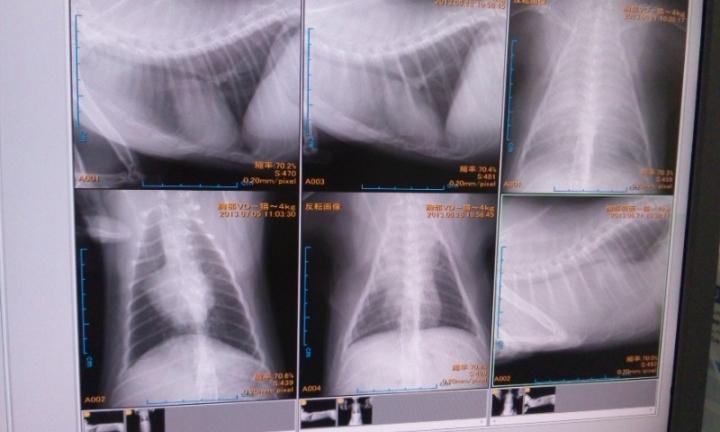

(レントゲン写真、無理な方はごめんなさい;;)

↑一番右が3週間前、一番左が今週

白いモヤモヤが悪いところですが、明らかに減り心臓がくっきり見えました!

右上と左下を比べると感動的な程、良くなってますー。。

でも、、

横になって寝れていた1週間後には一番右の状態になるということ。

気は抜けません。。